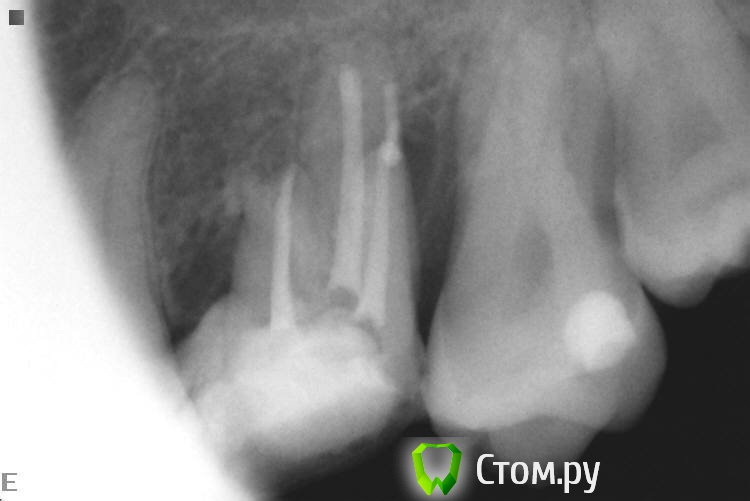

Slaggy Опубликовано 2 октября, 2014 Автор Поделиться Опубликовано 2 октября, 2014 Почётно ! Как извлекали ? Сколько по времени ? Почему без коффердама ? Руками, соник, ультрасоник, бино 3.5Гемор, если чесно, но я, вопреки мнению пациента полез в зуб на поиски МВ2, пришлось сделать все, чтоб исправить.4 посещения:1 - посмотрел на лунку, сказал что не она, полез в зуб, нашел мв2, снимок (не все удается скопировать, а база очень ограничена - неудачная программка стоит), непонравился МВ, прошел и снимок2 - прошел МВ2, сломал в МВ желтый Н, наломал кучу в МВ3 - достал все кроме первого (в клинике нет внутриканальных инструментов, решил принести свой эндочак и u-files)4 - принес свой чак, достал последний и запломбировал МВ и пломба. В клинике общий эндоинструмент, поэтому ломаки бывают непредсказуемые.В свой первый день тут я выкинул все. Весь ручной и машинный инструментарий - весь повитый был.Сейчас начальство стало прислушиваться (я ж их блатных лечу), скоро налажу все. 2 Ссылка на комментарий

Slaggy Опубликовано 2 октября, 2014 Автор Поделиться Опубликовано 2 октября, 2014 (изменено) Ну почётно,что тут скажешь. Вы сами знаете, что подтянуть. Но зуб я всё -таки покрыл бы в итоге,когда дойдёт до протезирования. Да все тянуть надо, при этом 10-12 пациентов в день.Сегодня 3 эндотрупа моляров работаны, Один свежий пульпит , 3 сдачи/фиксации, 1 съемник и 1 профгигиена. Про эндотрупы: ушел под кальцийКстати, это еще приличные снимки. обычно любуюсь апикальной третью корней ))))Тут в резорцинке косяк произошел. Видимо при конденсации проскочила гутта ((( расстроился.Но её хирург протежировал, Поговорю с ним, если апико сделает, то я не полезу. Изменено 2 октября, 2014 пользователем Slaggy 1 Ссылка на комментарий